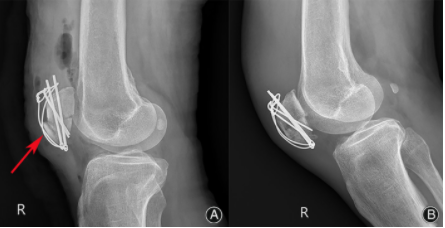

图4. 术后膝关节侧位x线片显示髌骨下极骨折块前移(红色箭头)(A)。术后1个月的侧位x线片显示骨折线模糊,向前移位的骨折块解剖复位(B)。